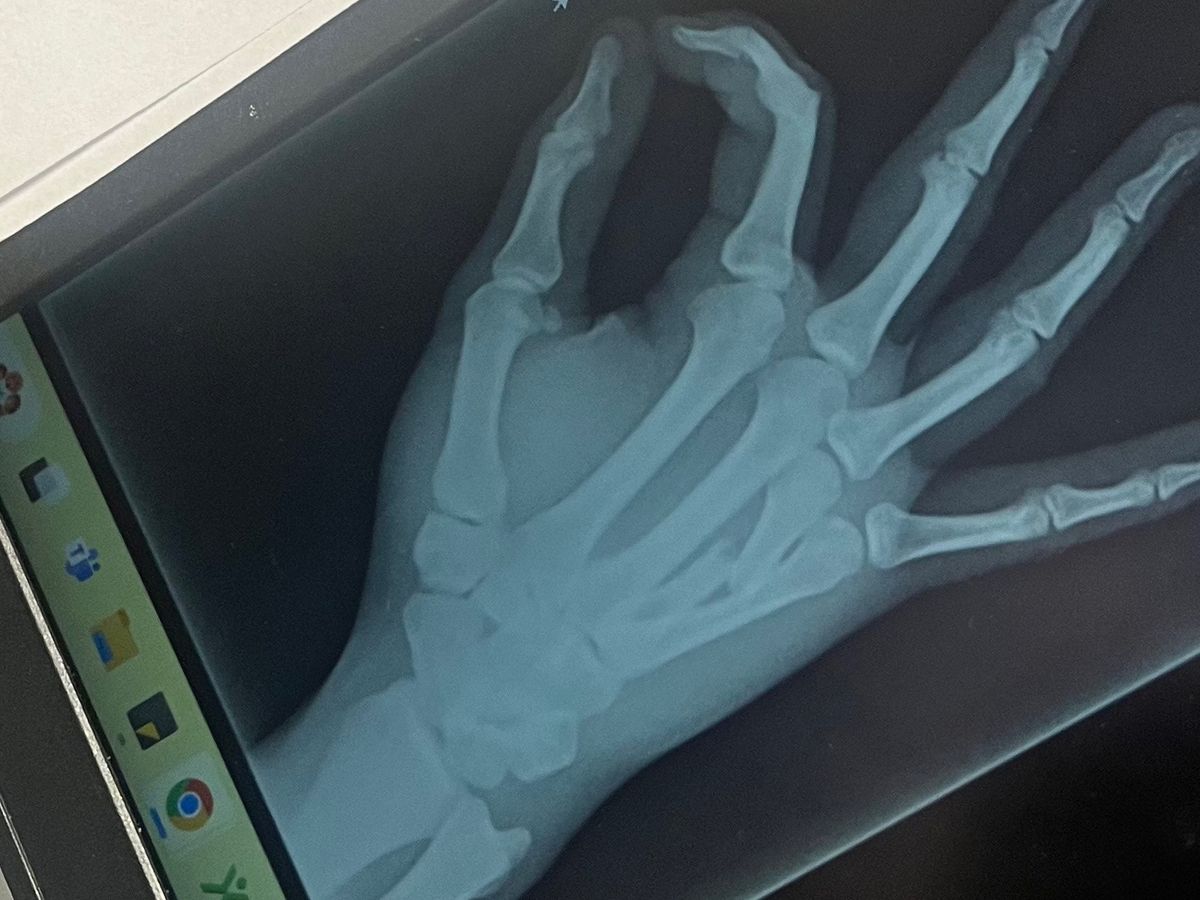

Hi everyone, I’m reaching out to ask for your help. My son, Bryson, recently broke his hand, specifically the third metacarpal, and he urgently needs surgery to fix it. The operation is scheduled for this Wednesday, but here's the challenge: since we're paying in cash, we need to cover the costs in advance by tomorrow.